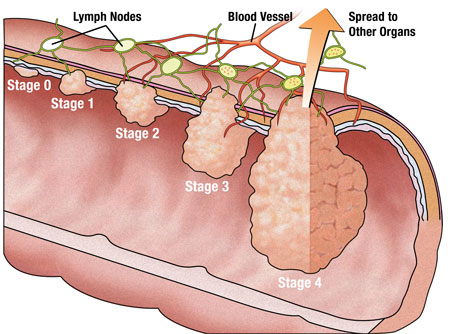

Kalýn Baðýrsak Kanseri diðer adý ile Kolorektal kanser (kolon ve rektum kanseri) ülke.. Detay

Kalýn Baðýrsak Kanseri diðer adý ile Kolorektal kanser (kolon ve rektum kanseri) ülke.. Detay

Bu bölümde kalýn baðýrsak kanserinin geliþimi ve neden önlenebilir bir hastalýk olduð.. Detay